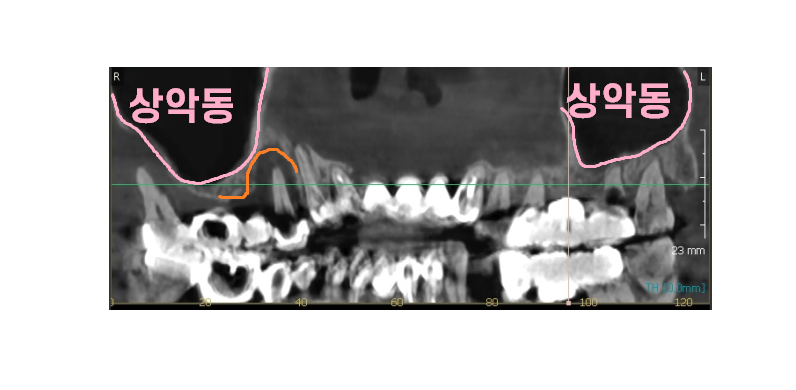

환자분이 궁금하신 부분은

"뼈이식"이 필요한지 여부였기 때문에

ct를 찍어 분석

답변을 드렸습니다.

230902

뼈이식 같은 경우는

보이지 않는 잇몸뼈 부분을 설명해야하다보니

임플란트는 해야는걸 알겠어

근데 뼈이식은 과잉진료 아닌가? 생각하실 수 있습니다.

구강 내부 상태를 볼 수 있는 ct를 보여드리면서

최대한 자세히 설명드렸죠.